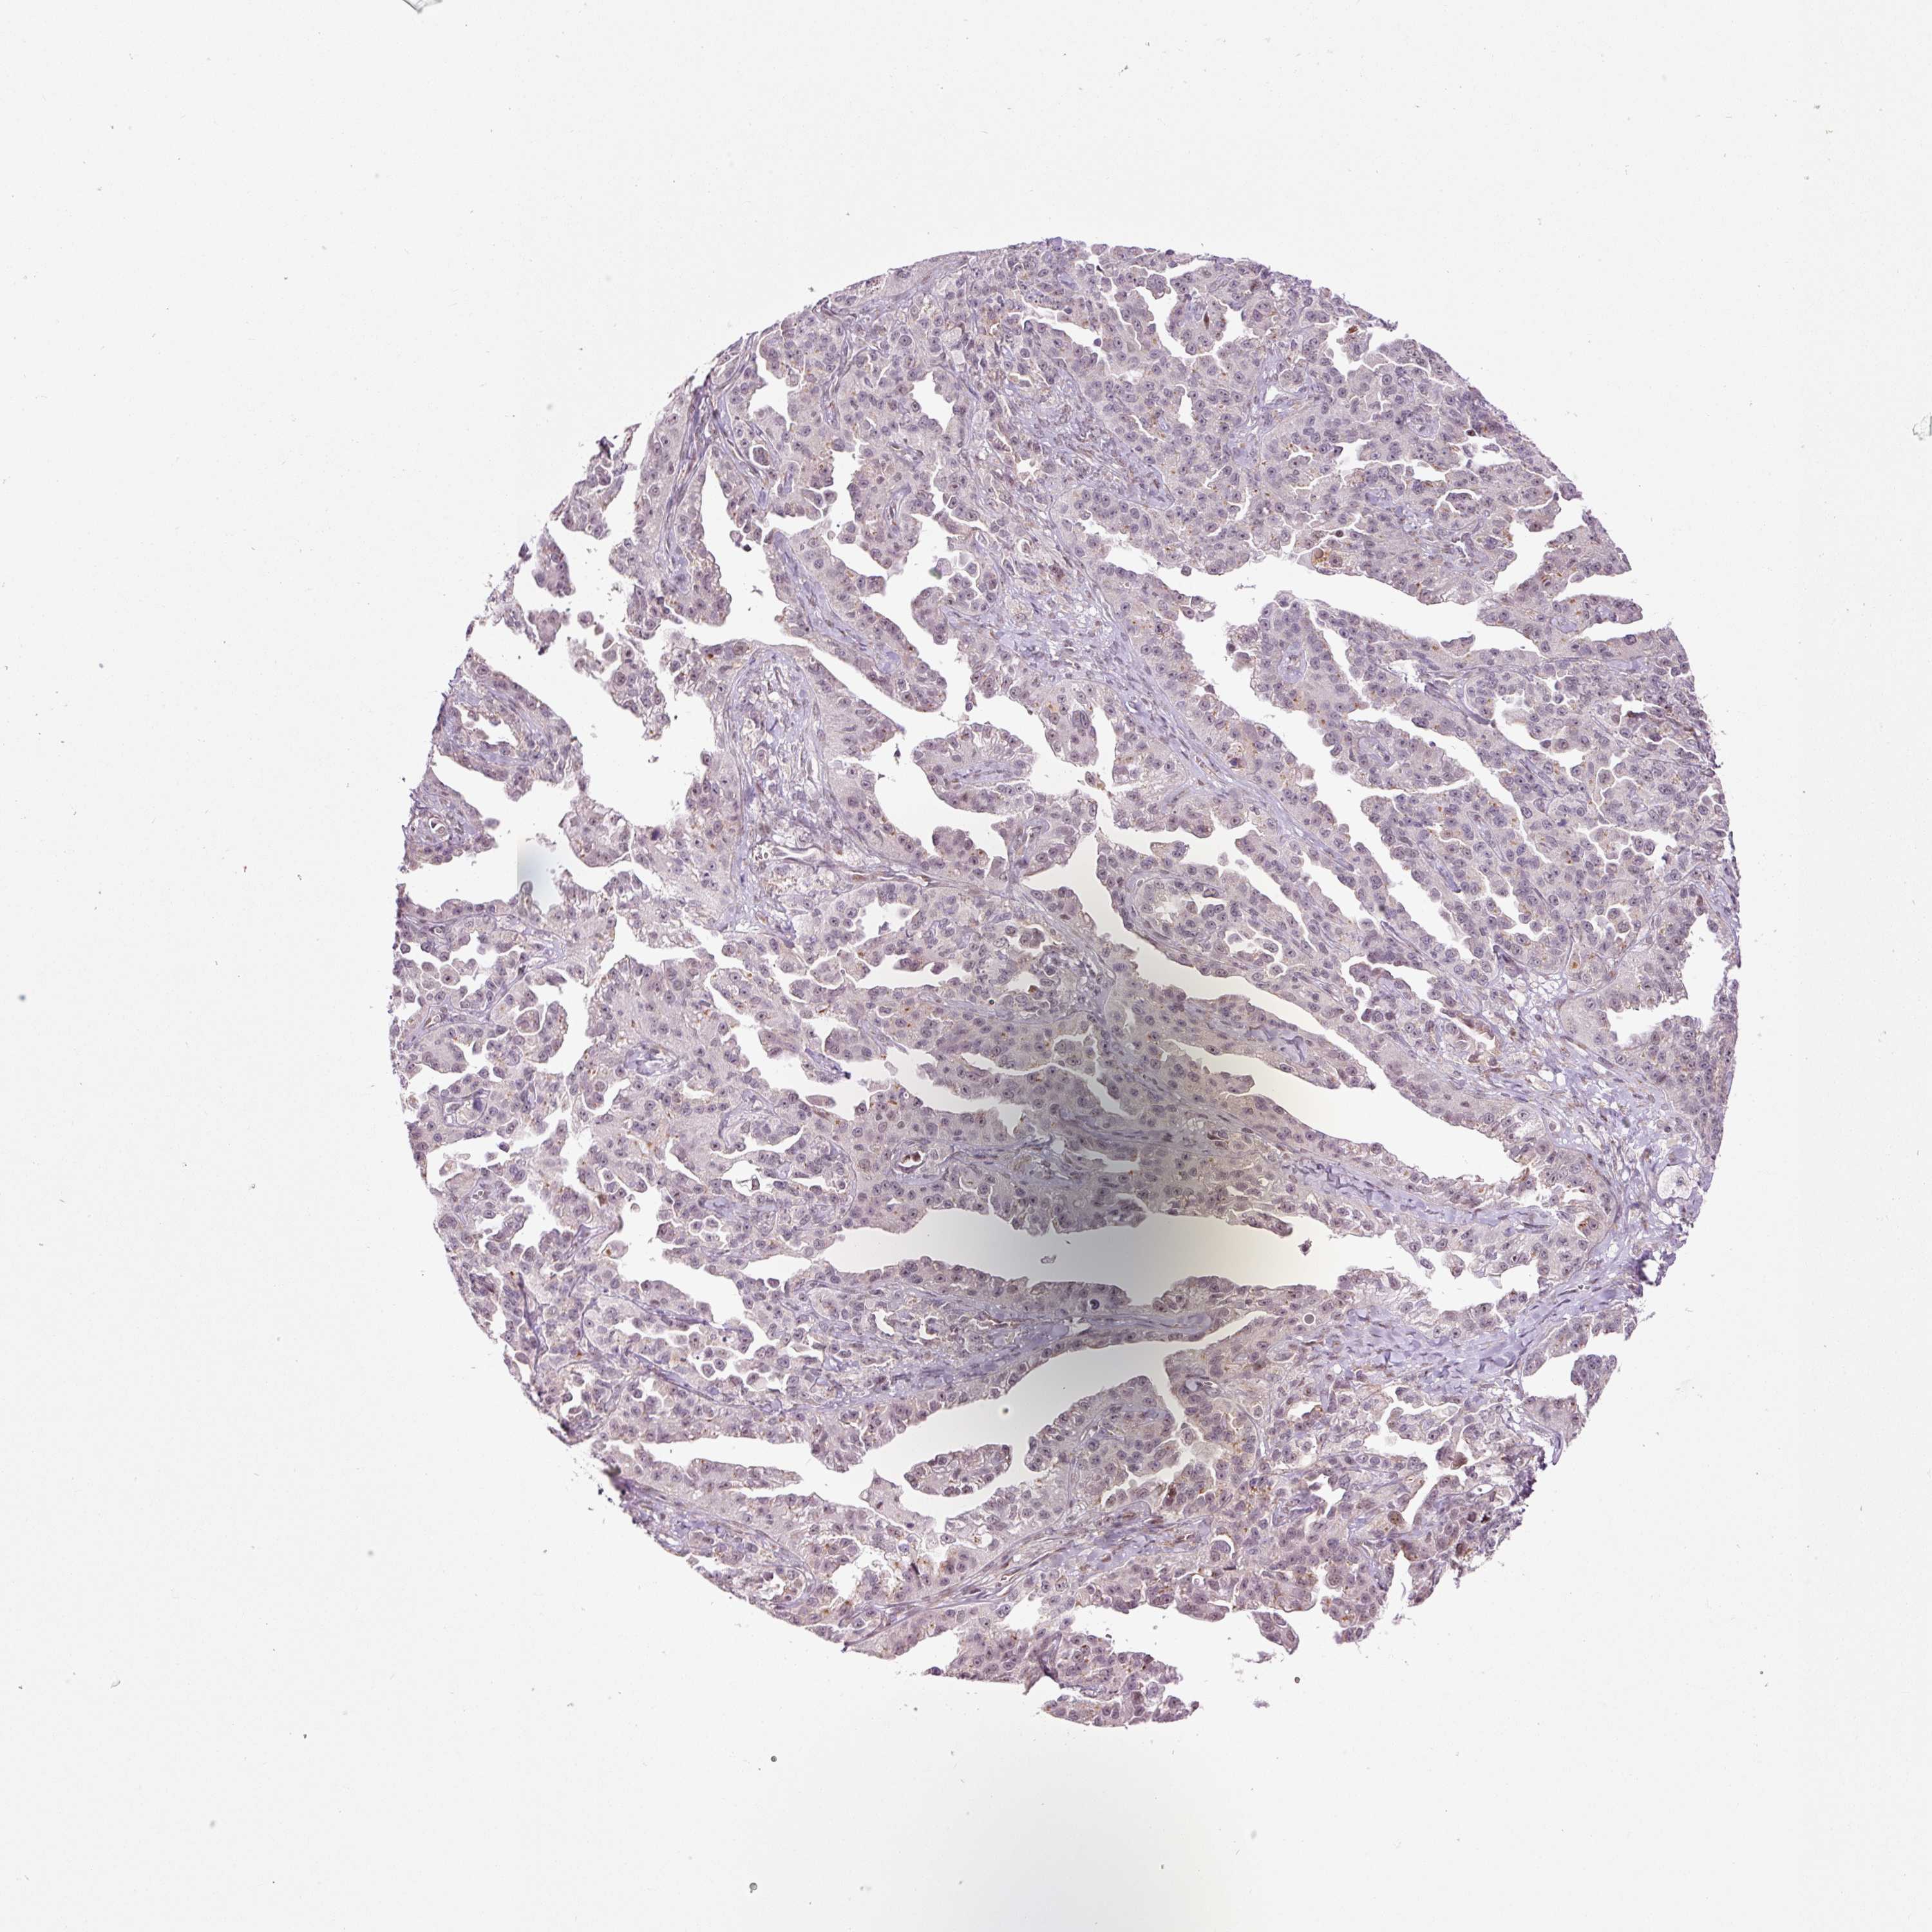

OVARIAN CANCER - Protein expressioni

A mouse-over function shows sample information and annotation data. Click on an image to view it in a full screen mode. Samples can be filtered based on level of antibody staining by selecting one or several of the following categories: high, medium, low and not detected. The assay and annotation is described here.

Note that samples used for immunohistochemistry by the Human Protein Atlas do not correspond to samples in the TCGA dataset.

Antibody stainingi

Antibody staining in the annotated cell types in the current human tissue is reported as not detected, low, medium, or high, based on conventional immunohistochemistry profiling in selected tissues. This score is based on the combination of the staining intensity and fraction of stained cells.

Each image is clickable and will lead to virtual microscopy that enables deeper exploration of all samples and also displays staining intensity scores, fraction scores and subcellular localization as well as patient and tissue information for each sample.

Cystadenocarcinoma, serous, NOS

Cystadenocarcinoma, mucinous, NOS

Adenocarcinoma, NOS

Carcinoma, endometroid

Carcinoma, NOS